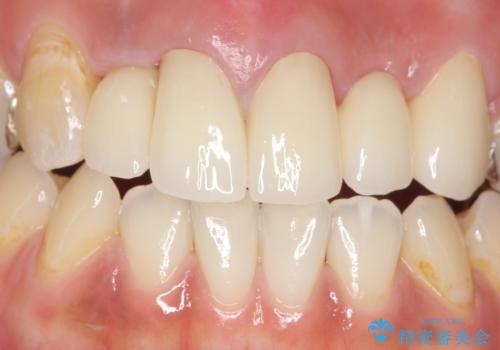

- 昔入れた被せ物と歯茎の間の隙間が気になると来院された方の症例です。

右上1、2番目の歯と左上1、2、3、番目の歯のブリッジを除去し、オールセラミッククラウンによる補綴を行うことで見た目を改善しました。

今回用いたオールセラミッククラウンはジルコニアフレームという白い素材の上にセラミックを盛っているため、審美性が非常に高いのが特徴です。

また、ジルコニアは人工ダイヤモンドの材料にも使われているほど高い強度を持っており、そのためオールセラミッククラウンは審美性だけでなく、奥歯やブリッジの補綴も可能とするクラウンです。